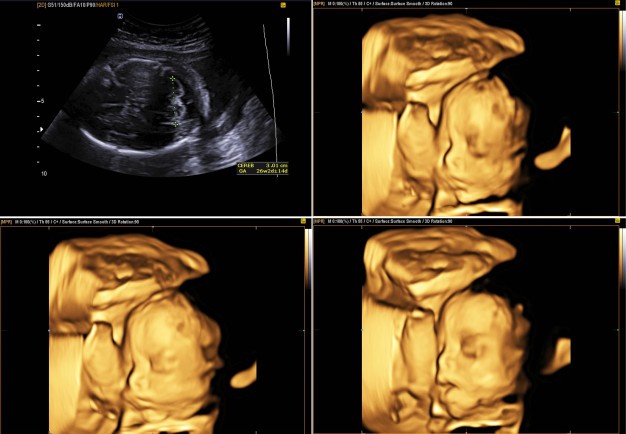

La tecnica ecografica tridimensionale (3D) con sonda transaddominale o transvaginale è una tecnica all’avanguardia in campo ostetrico e ginecologico, in quanto consente l’acquisizione volumetrica delle immagini ecografiche bidimensionali come la RMN e la TC.

Numerosi studi hanno constatato come l’ecografia 3D applicata all’ostetricia possa integrarsi all’ecografia bidimensionale (2D) nella valutazione di un feto che presenta malformazioni e anomalie degli arti e dei difetti del tubo neurale.

Questa innovativa tecnologia consente di ottenere immagini più definite, quindi vedere il bambino in modo più chiaro, evidenziando meglio alcuni organi interni.

Grazie all’ecografia 3D, è possibile valutare i volumi degli organi fetali, stabilendo una correlazione con l’accrescimento fetale.

Per ottenere un esame più dettagliato, è necessario che il feto sia posizionato adeguatamente e che ci sia parecchio liquido amniotico. In questo modo, l’ecografia 4D mostrerà tutto ancora più nitidamente.

Il periodo migliore per eseguire l’ecografia 4D è compreso fra la 23-24° e la 28-29° settimana di gestazione, anche se già nel primo trimestre è possibile eseguire l’esame in 3D o 4D.

L’ecografia 4D, talvolta, consente nell’immediato di percepire diverse espressioni del feto come sbadigliare, deglutire, succhiare, fare smorfie, sorridere, o battere le ciglia.

Inoltre, sono percepibili diversi movimenti come stiramento, flessione della testa, movimenti isolati delle braccia o delle gambe.